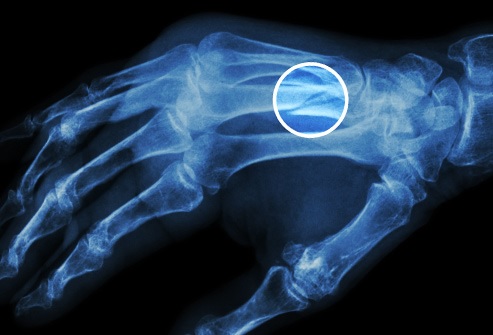

Gout

This condition shows up as a sudden pain and swelling in one of your joints, often a big toe. It’s a form of arthritis caused by a buildup of uric acid in your body. If you take certain medications for high blood pressure, eat red meat and shellfish, and have more than two alcoholic drinks a day, you’re at higher risk. The soda sweetener known as fructose also raises your risk, and so does obesity.